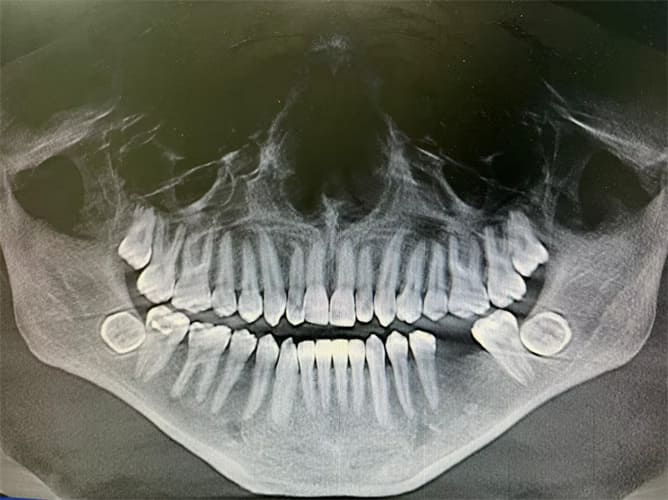

An impacted tooth is one that fails to erupt (come through the gums) at the expected time because it’s partially or completely trapped in the jawbone or beneath the gum tissue. In simple terms, the tooth is stuck and unable to move into its correct position naturally.

Impaction most often affects canine teeth (eye teeth) and wisdom teeth, but it can occur with any tooth.

At Smiles in Motion Orthodontics, we use digital X-rays and 3D imaging to precisely locate impacted teeth and plan the best treatment strategy. Depending on the case, treatment may include: